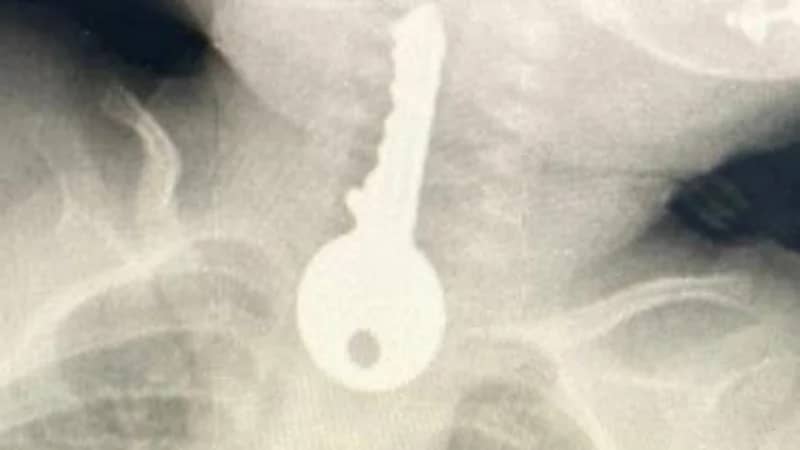

مفتاح سيارة كاد ينهي حياة أربعيني في القنفذة

نجاة طفل من الموت بأعجوبة بعد ابتلاعه “مفتاح” بالطائف